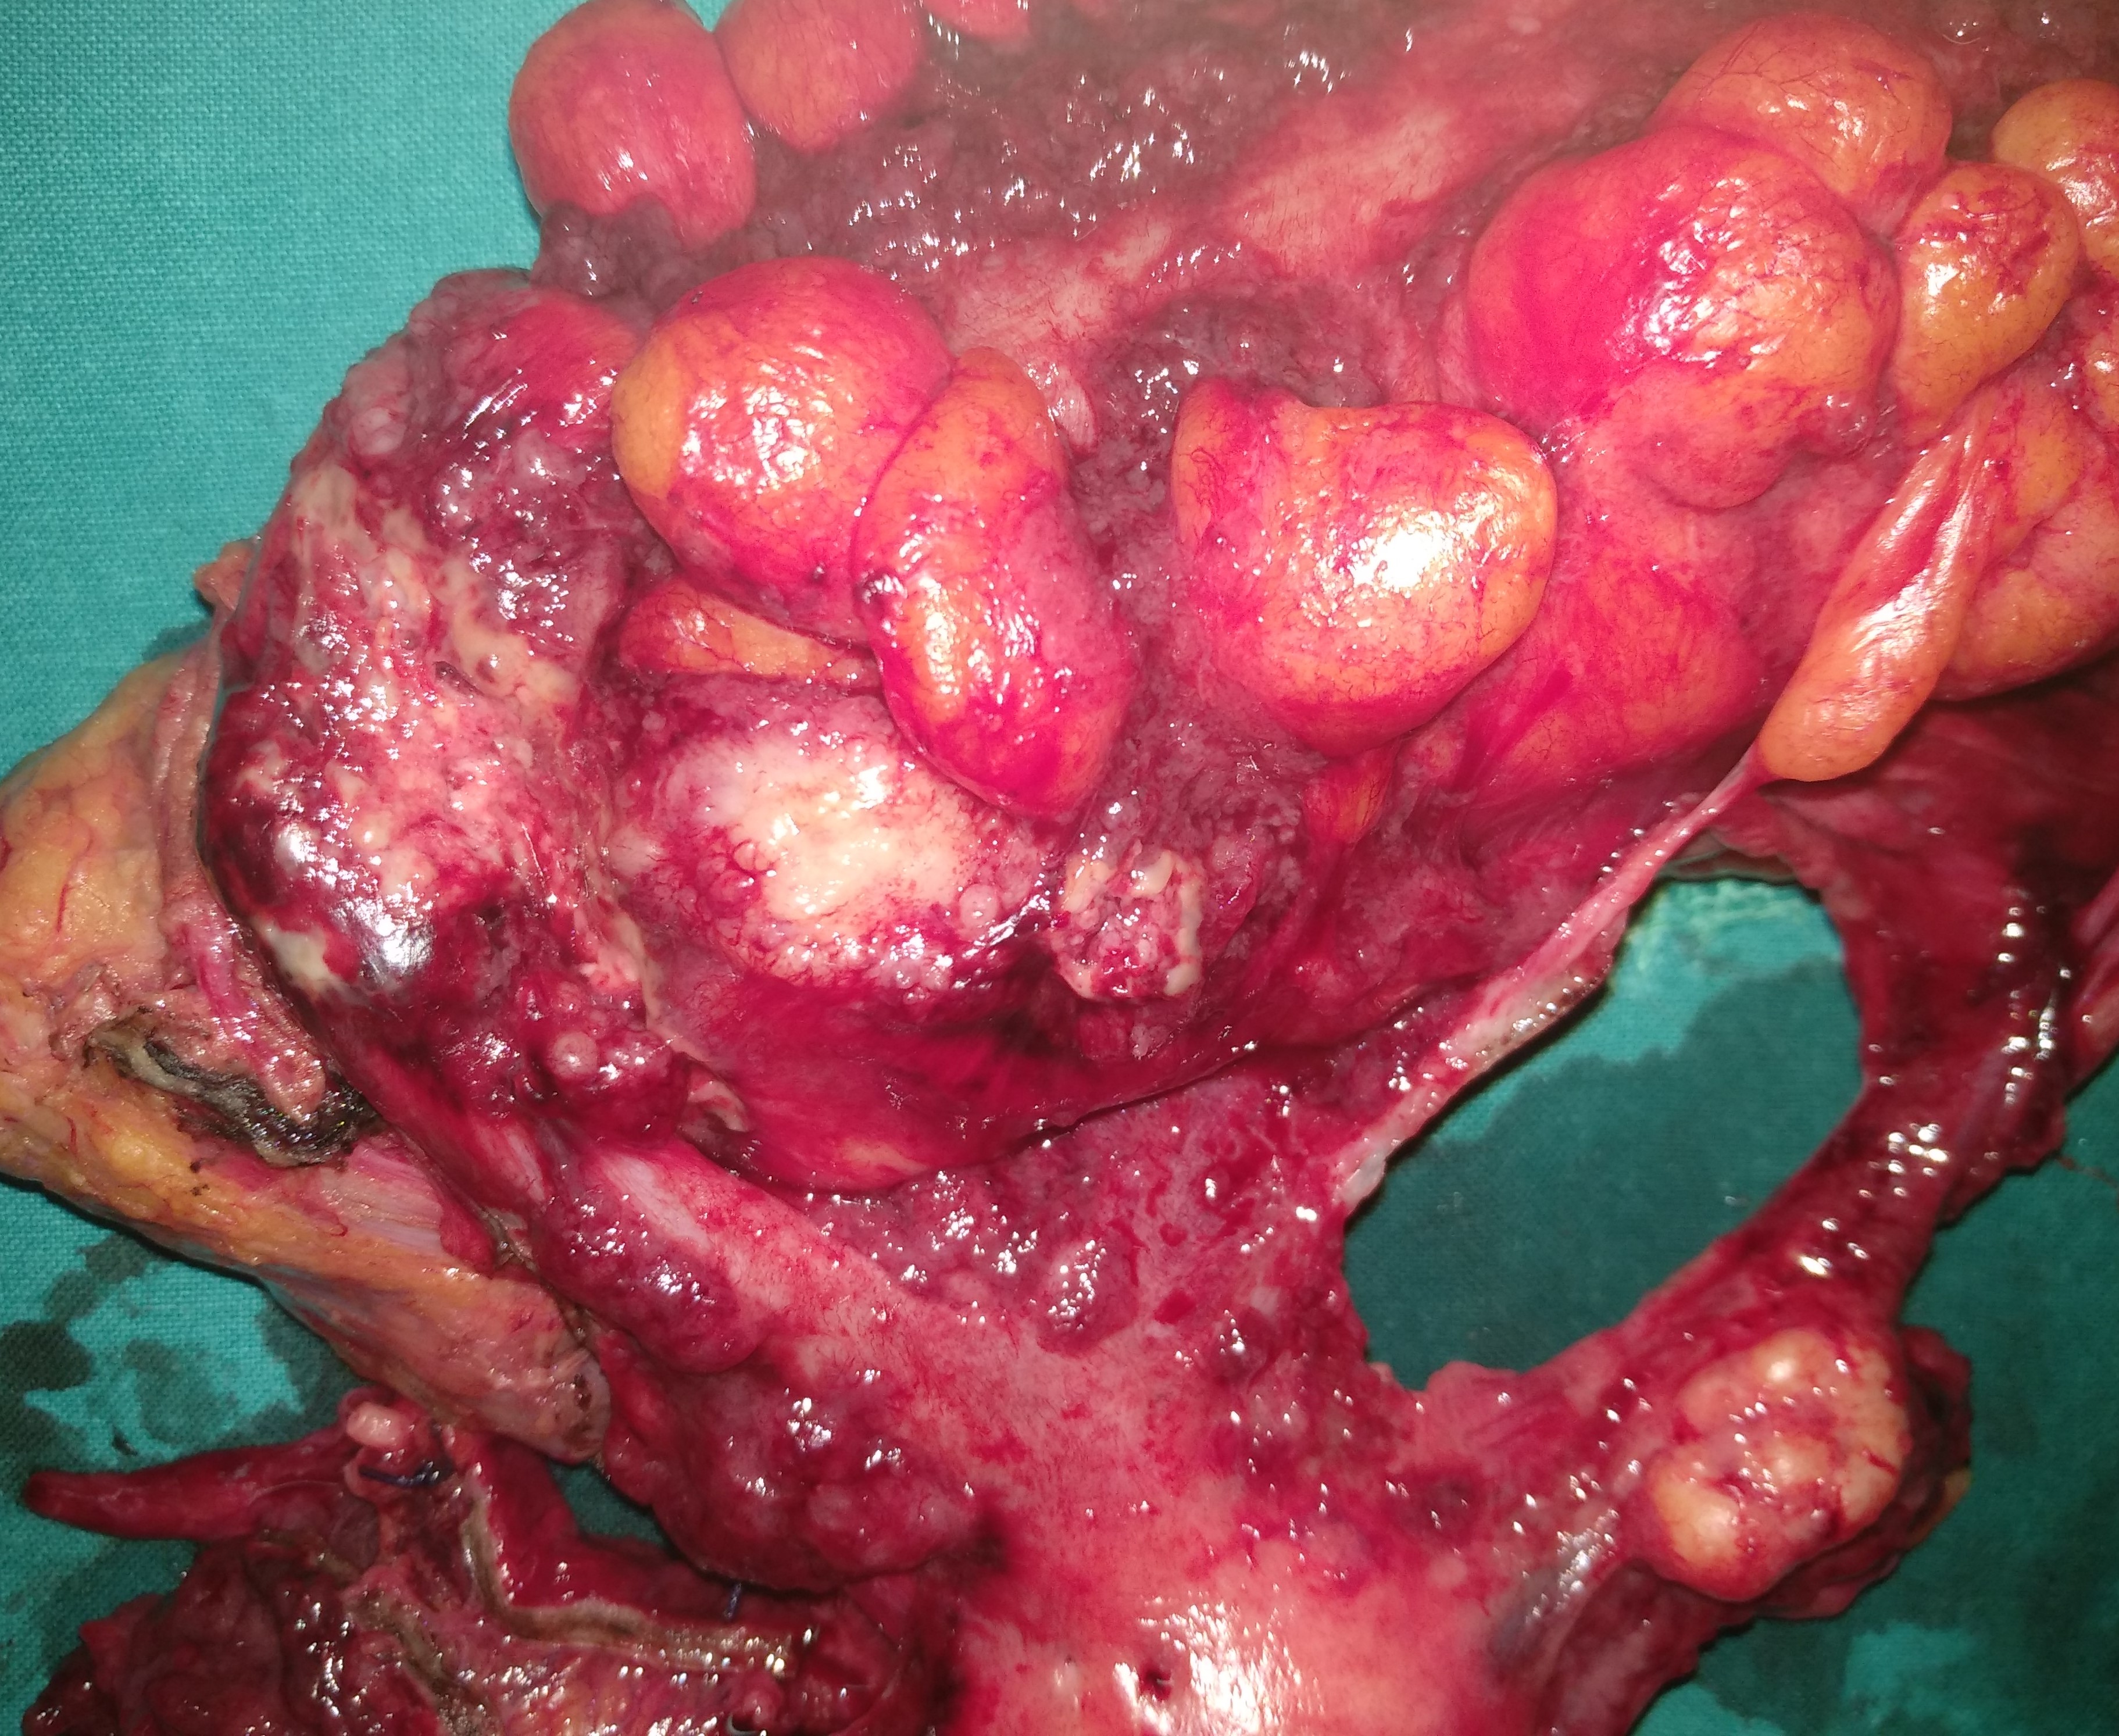

Resected obstructed ileal loop. Blue circles enclose the metastatic foci (Courtesy Dr. V. Penopoulos)

The two metastatic foci causing stenosis and bowel obstruction are clearly visible (Courtesy Dr. V. Penopoulos)

After opening the specimen, the metastatic foci are clearly visible (Courtesy Dr. V. Penopoulos)